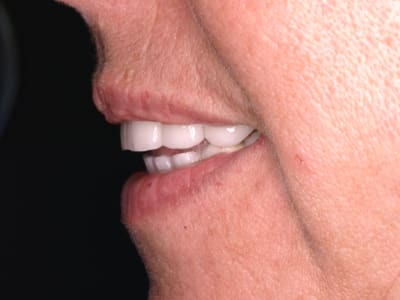

bridge zircon haut et bas . le jour de la pose

ce n était pas mon labo , et je trouve ça un peu rustique .

mais en tout cas aujourd’hui , soit 10 ans après c est tjs là

Elle peut te remercier car vu le cas au debut c est sympathique le résultat

Peut etre comme tu dis un peu d animation esthétique aurait été un plus mais bon à 10 ans encore la c est beau

pardon , ce n est pas le jour de la pose , ç est l essayage et la simulation des longueurs . on y voit les coups de fraise .

ceci dit , ce n etait guerre plus joli apres .